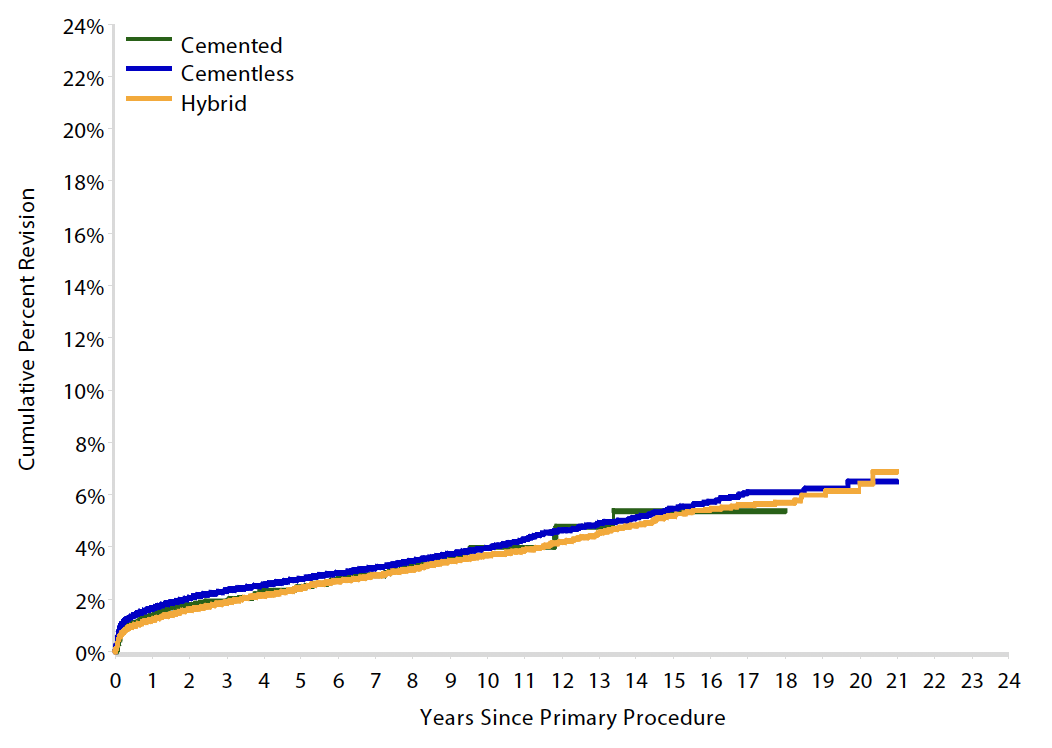

Australian Joint Registry 2023

- 15 year revision rate

- collared 5.3%

- collarless 6.0%

Results

Australian Joint Registry 2023 Revision rates by fixation (400,000 THA)

| Cemented | Uncemented | Hybrid | |

|---|---|---|---|

| 5 year | 2.6 | 3.0 | 2.6 |

| 10 year | 3.8 | 4.3 | 3.9 |

| 15 year | 5.1 | 5.9 | 5.3 |

| 20 year | 7.0 | 6.7 |

15 year revision rate by age

64 - 74 year > 75 years

| Cemented | Uncemented | Hybrid | |

|---|---|---|---|

| < 55 | 6.4 | 7.2 | |

| 55 - 64 | 6.2 | 5.5 | 6.1 |

| 65 - 74 | 5.4 | 5.5 | 5.2 |

| > 75 | 3.3 | 6.8 | 4.7 |